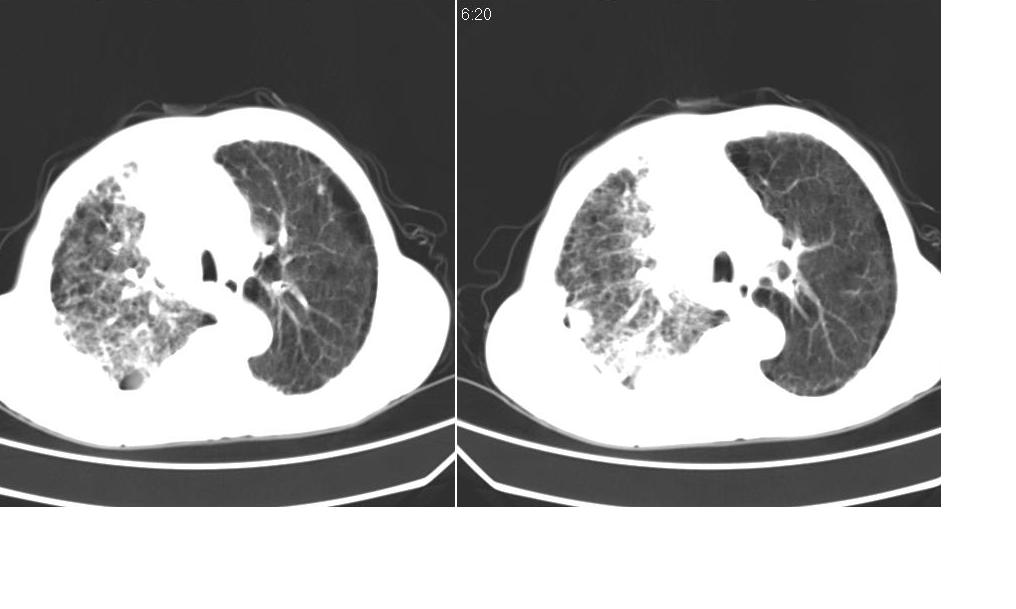

以下是引用zsl6918在2008-5-3 19:53:00的发言:[br]右肺中心型肺癌并纵隔淋巴结转移,胸膜转移,右肺癌性淋巴管炎。

以下是引用liuyue在2008-5-3 20:49:00的发言:[br]1.右侧中心型肺癌伴双肺转移瘤、纵隔淋巴结转移、右侧胸腔积液(侵及胸膜所致可能性大)。[br]2.右肺阻塞性肺炎,癌性淋巴管炎不除外。

以下是引用mzh123在2008-5-3 21:12:00的发言:[br]本人持有不同观点[br]1、右肺似有团块表现,但只有一个层面,所以本人认为还是以片为主,所以不能首先考虑肿瘤[br]2、右肺普遍成纤维化改变 并伴有片状炎症改变,和癌性淋巴管炎表现不同[br]3、所以本人认为是间质纤维化伴感染可能大 及胸腔积液